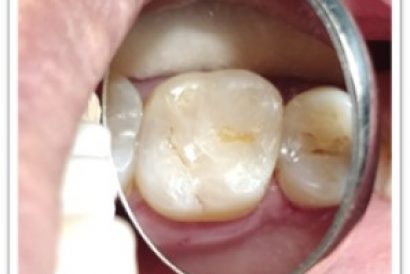

Patient Name:Chaitrali Patel

Tooth Involved :46

Diagnosis :Caries Involving Enamel And Dentin Approaching The Pulp : Sympotomatic Reversible Pulpitis

Treatment :Direct Pulp Capping With MTA

Restoration: Direct Composite Restoration Using Nanohybrid Composite

Before

After